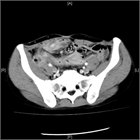

1. クローン病とは、原因不明の、口腔内から肛門周囲までの腸管のどの部位にでも発症する炎症性腸疾患の1つである。